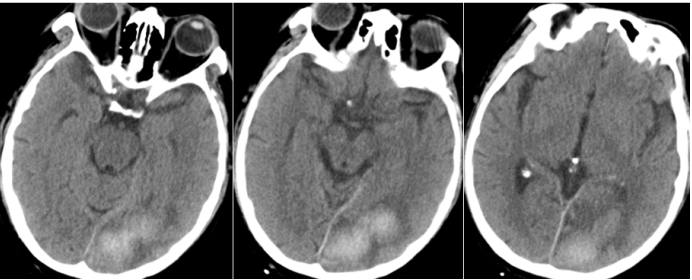

治疗2天后带患者外出做头胸部CT:考虑左侧枕叶脑出血(图5),建议短期复查除外其他;双肺磨玻璃影伴斑片影,考虑多发感染(图6)

图片

图5 头部CT(2023-02-03)

图6  胸部CT(2023-02-03)

2023年2月11日头部CT显示病灶较2月3日有所吸收(图10),胸部CT示双肺磨玻璃影和实变影较前减少(图11)

图10  头部CT(2023-02-11)

图11  胸部CT(2023-02-11)